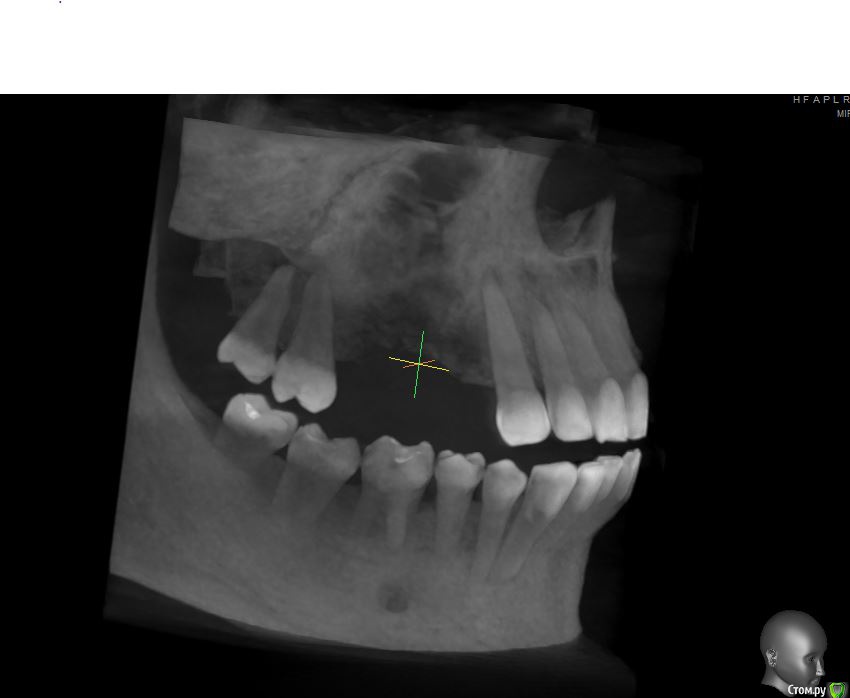

jm3300 Опубликовано 12 июля, 2016 Автор Поделиться Опубликовано 12 июля, 2016 А до операции КТ могли бы выложить? И сколько времени отсутствовали зубы в этой области?отсутствовали достаточно долги. КТ до: Ссылка на комментарий

jm3300 Опубликовано 14 июля, 2016 Автор Поделиться Опубликовано 14 июля, 2016 выкладываю кт Ссылка на комментарий

умножающий печаль Опубликовано 14 июля, 2016 Поделиться Опубликовано 14 июля, 2016 Промыть пазуху через соустье, курсом. Я отправляю к ЛОРам. Антибиотикотерапия, гипосенсибилизация. Один из винтов вестибулярно без костной поддержки, на мой взгляд. 1 Ссылка на комментарий

jm3300 Опубликовано 14 июля, 2016 Автор Поделиться Опубликовано 14 июля, 2016 Промыть пазуху через соустье, курсом. Я отправляю к ЛОРам. Антибиотикотерапия, гипосенсибилизация. Один из винтов вестибулярно без костной поддержки, на мой взгляд. гайморит всё таки есть? 1 Ссылка на комментарий

syrovovec Опубликовано 15 июля, 2016 Поделиться Опубликовано 15 июля, 2016 (изменено) Пазуха чистая, Антон, какой винт на выход не понял?Может у пац аллергия ? Изменено 15 июля, 2016 пользователем syrovovec 1 Ссылка на комментарий

kladoffka Опубликовано 15 июля, 2016 Поделиться Опубликовано 15 июля, 2016 Тоже не понял, вроде все хорошо стоят. Главное слизистые то в покое. 1 Ссылка на комментарий

умножающий печаль Опубликовано 15 июля, 2016 Поделиться Опубликовано 15 июля, 2016 (изменено) гайморит всё таки есть?Судя по симптоматике, которую вы представили, есть. На снимке признаки могут запаздывать, ежели процесс острый, хотя снижение пневматизации должно быть заметно. Я на мониторе не разглядел. Рентген всего лишь доп. метод обследования. Диагноз ставит врач, то есть вы, сопоставив клинику и доп.методы.З.Ы. Я не думаю, что в вашем случае причина гайморита имплантация. Временной интервал слишком велик. Изменено 15 июля, 2016 пользователем умножающий печаль 1 Ссылка на комментарий